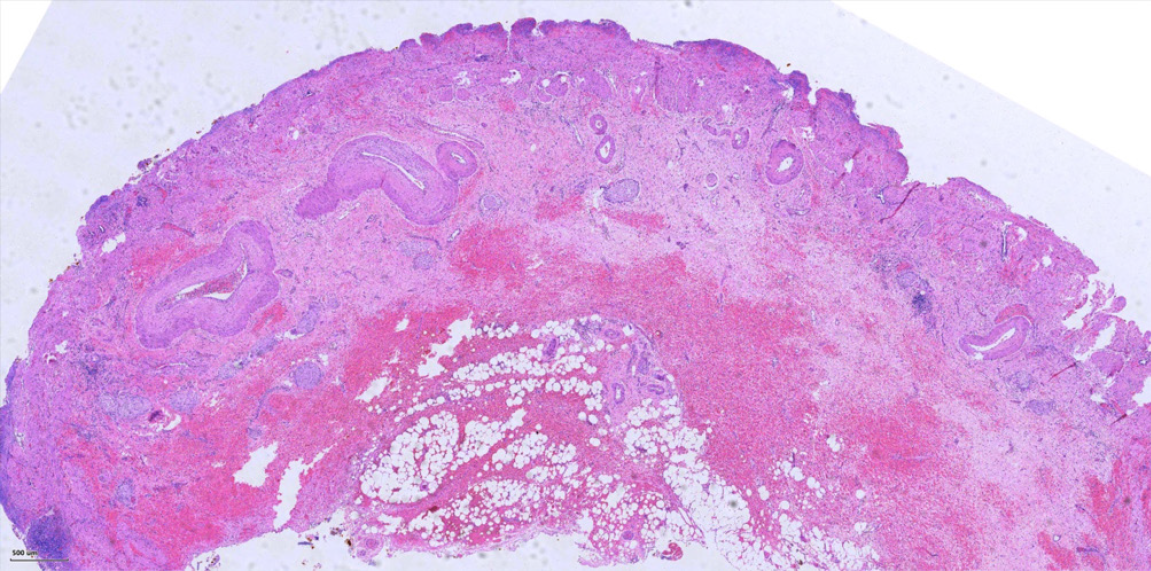

Figure 5

Figure 5  Histopathology of the resected gallbladder (HE stain, × 40 magnification), showing chronic cholecystitis with mucosal epithelial denudation, necrosis, and transmural hemorrhage.